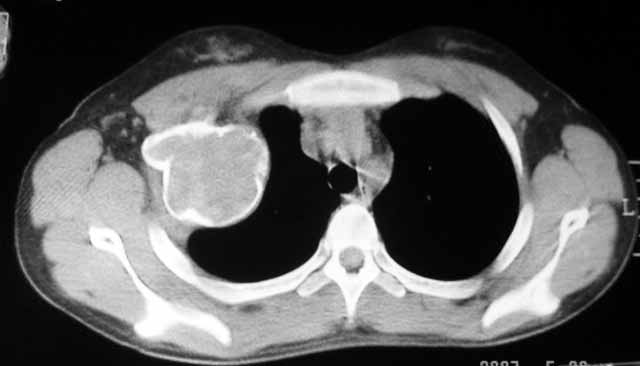

以下是引用dyqct在2007-5-26 12:01:00的发言:[br]右第二肋腋侧呈明显膨胀性、分叶状改变,内无明显间隔,ct值49hu,病变大小约67x57mm,周围硬化缘无断裂,内缘见多数骨嵴,肿块与正常骨间界限清楚。无移行带。周围软组织无浸蚀,胸膜腔无积液。[br]考虑:1、右第二肋动脉瘤样骨囊肿可能性大;[br] 2、需同骨巨细胞瘤、浆细胞瘤、骨纤鉴别。